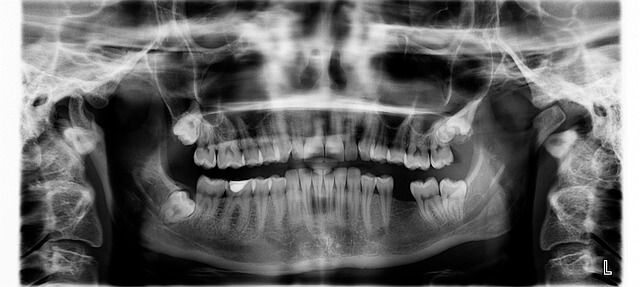

* 잇몸이 내려 앉을 때 가장 먼저 느껴지는 건 시린 통증입니다. * 제가 직접 주변 사람들과 이야기를 나눠 보니 단순히 미용적인 걱정을 넘어서, 따뜻한 음식조차 편하게 즐기지 못하는 불편함이 컸습니다. * 잇몸이 내려 앉을 때 치아 뿌리가 노출되면 세균에 더 쉽게 노출되므로, 장기적으로는 치아 건강 자체도 위협받습니다. * 결국 잇몸 복원치료가 필요한 이유는 단순히 보기 좋게 만드는 게 아니라 평생 치아를 지키기 위한 중요한 선택이라는 점입니다.

- * 치아 뿌리 노출로 인한 세균 위험